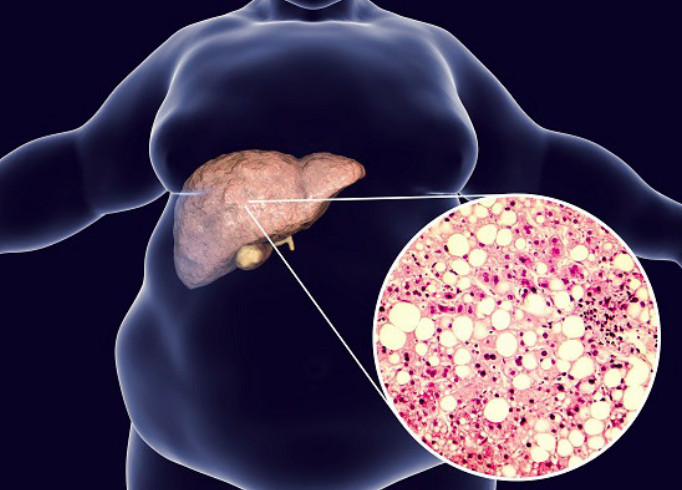

지방간은 간에 지방이 과도하게 축적된 상태를 나타내는데, 지방간 상태가 되면 피로가 누적되고 회복 속도가 느려질 수 있습니다. 지방간을 무시하고 방치하게 되면 심각한 간 질환으로 진전할 수 있으므로 주의가 필요합니다. 오늘은 지방간 없애는 방법에 대해서 자세히 살펴보도록 하겠습니다.

지방간은 간세포에 지방이 무리하게 축적되면 발생하는 질병입니다. 이러한 지방간은 최근들어 그 발병률이 올라가 주변에서 흔히 관찰되는 질병 중 하나가 되었습니다. 지방간은 절대 경시해서는 안 되며, 방치 시 심각한 합병증이나 간암으로 진행될 수 있습니다. 약 4명 중 1명이 지방간에서 간경변증으로 진행되는데, 이럼에도 불구하고 많은 사람들이 지방간을 대수롭지 않게 여기는 경향이 많습니다.

지방간은 만성 염증 증상으로 간 조직이 섬유화되어 간 기능이 손상됩니다. 이에 따라 복수, 간성뇌증, 황달, 정맥류 출혈과 같은 합병증이 발생할 수 있습니다. 음주가 지방간과 많은 연관이 있는데, 남성은 일주일에 3~4병, 여성은 2병 정도의 주량으로 소주를 마시면 지방간 발생 가능성이 높아진다고 합니다.